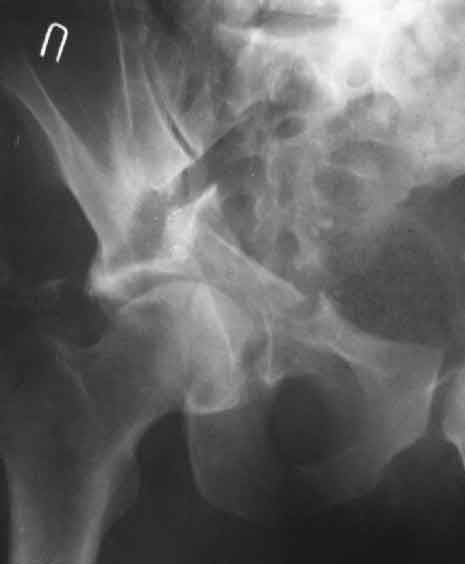

Дополнение, минимальный набор необходимых прекций, необходимых для лечения повреждений вертлужной впадины

Фас. Inlet

Подвздошная Запирательная